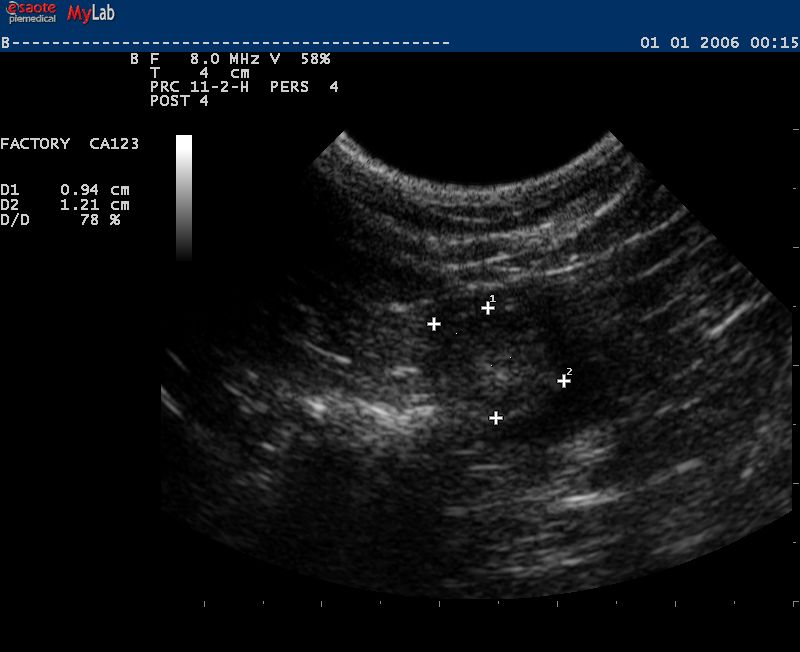

Auch in der Veterinärmedizin wird das schonende Verfahren der Ultraschalldiagnostik zunehmend eingesetzt. Wir verwenden es im Bereich der Abdominal- und Trächtigkeitsdiagnostik .